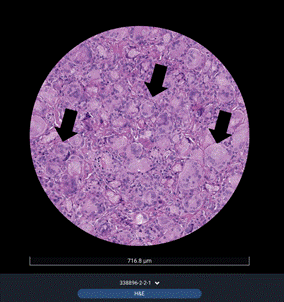

Однако наиболее информативное подтверждение эффективности введения плазмы, обогащенной тромбоцитами, получено при сравнительном гистологическом анализе биоптатов, полученных до и после курса лечения. Характерной особенностью патоморфологической картины (рис. 4) гранулем после введения ИТН на основе ПМК является большое количество клеток инородного тела со специфическими включениями.

Рис. 4. Патоморфологические изменения в гранулеме дермы области шеи пациентки К., 42 лет (фиксация материала в 10%-ном нейтральном формалине, парафиновый срез 5 мкм), до курса плазмотерапии. Световая микроскопия. Окраска гематоксилином и эозином. Увеличение ×200. Репрезентативный биоптат до лечения. Визуализируется классическая гранулема инородного тела с плотным лимфо-гистиоцитарным инфильтратом, многочисленными гигантскими клетками инородных тел (черные стрелки) с округлыми включениями (соответствуют морфологии частиц инъекционного тканевого наполнителя). Составлено авторами по результатам данного исследования